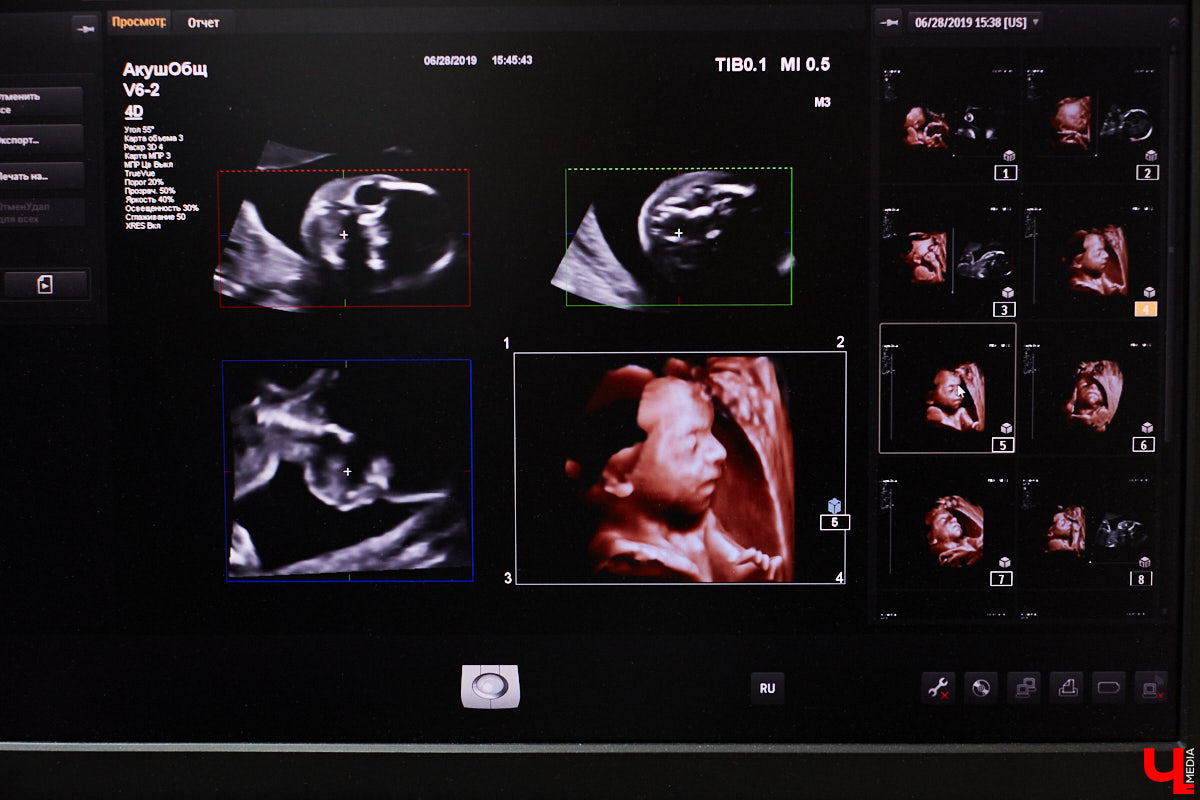

Есть во Владимире специалисты, которые считают своим долгом не просто ходить на работу по расписанию, а поддерживать, курировать пациентов, изучать методы их эффективного лечения. Так о своей деятельности говорит и Сергей Голяков, врач широкого профиля. Гинеколог, онколог, маммолог, врач ультразвуковой диагностики — он каждый день сталкивается с разными случаями и страшными для многих диагнозами. «Ключ-Медиа» поговорил с экспертом о профилактике, высоких технологиях и стереотипах в профессии.

Ежедневный прием у доктора Голякова подразумевает около 20 человек. Больничные «встречи» — смешанные: это и ультразвуковая диагностика от макушки до пяток, и гинекологическая помощь. Формат стационара, в котором работает Сергей, очень нравится специалисту, ведь так можно сразу заручиться консультацией коллег, выбрать максимально быстрый и верный путь решения проблемы.